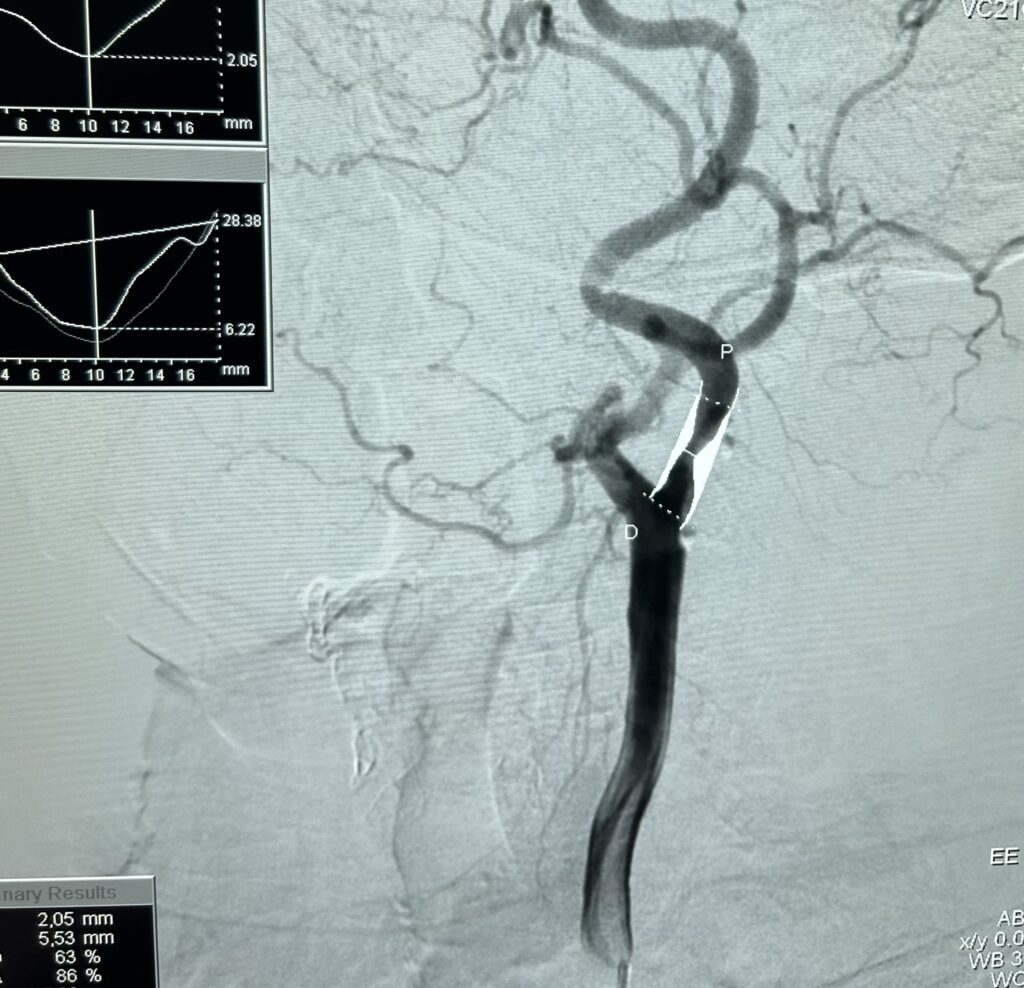

Tratamentos Endovasculares: Esta abordagem revolucionária permite tratar as doenças vasculares “por dentro” do vaso, sem a necessidade de grandes incisões. Através de uma pequena punção na pele, inserimos dispositivos como cateteres, fios-guia, balões e stents para reparar vasos sanguíneos. Esses procedimentos podem ser usados para desobstruir artérias estreitadas, tratar aneurismas, ou corrigir problemas nas veias. Contempla o tratamento tanto das doenças arteriais (como isquemia de membros) quanto das doenças venosas. A principal vantagem é a menor agressividade, resultando em menos dor, cicatrizes mínimas e um tempo de recuperação significativamente menor para o paciente. Especificamente nos casos de doença arterial, as cirurgias são de maior porte e em geral os pacientes possuem outras comorbidades que o tornam mais frágil, portanto, a técnica endovascular revolucionou o tratamento das doenças vasculares. Possibilitando uma recuperação muito mais rápida, com menos dor e menos agressão ao organismo do paciente. Essa inovação transformou a forma como tratamos problemas como aneurismas e obstruções, tornando os procedimentos mais seguros e acessíveis a um número maior de pessoas, aumentando a qualidade de vida e expectativa de vida deste grupo de pacientes.